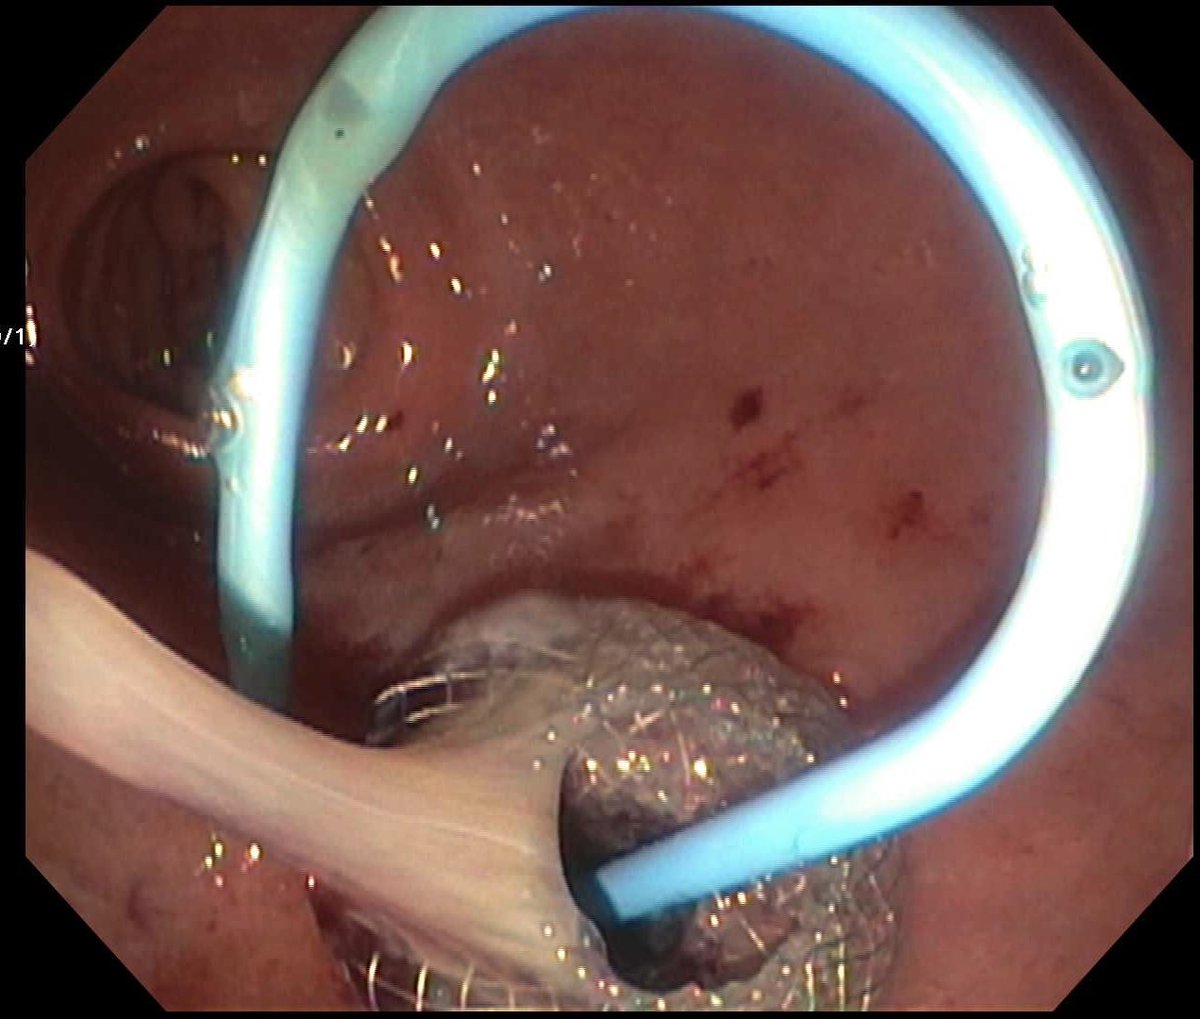

Biliary drainage via EUS-guided hepaticogastrostomy for distal MBO after failed ERCP. EUS continues to redefine what’s possible in GI intervention

Precision. Palliation. Progress.